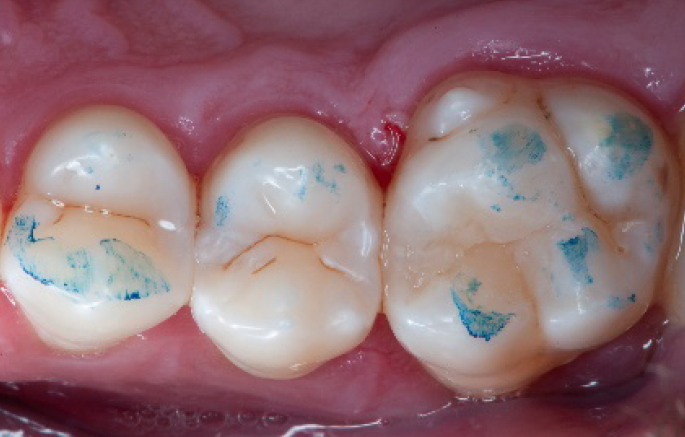

Step 6:

Selective enamel etching procedure with Conditioner2.

Step 7:

Adhesive application with a universal adhesive, Prime&Bond3.